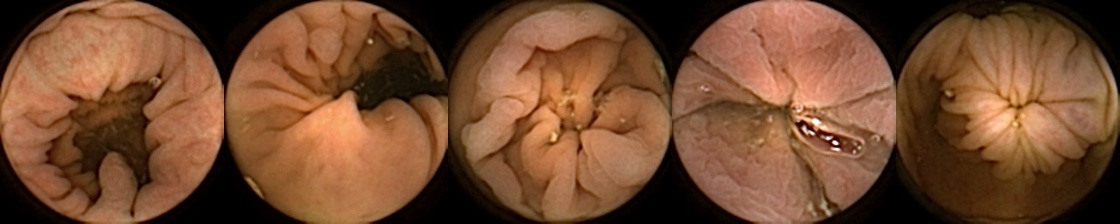

Figure 3 shows classification output examples for the MIV model using the pretrained ConvNext. Note that the model has a test accuracy of 83.66% for DBA L2 with 2 heads. In each row, the leftmost image is the query and the four images to the right of each query are the target images. The True Positive (left-top) and True Negative (bottom-right) examples outline the cases when the model is able to successfully distinguishes images containing unique polyps from those with dissimilar polyps. The False Negative (top-right) and False Positive (bottom-left) examples show the cases where the model fails to correctly distinguish images of unique polyps and images of dissimilar polyps. Further, we can note from the differences in the examples of True Positives and False Negatives that when the query image and the target set instances differ from each other in some ways, then the model can misclassify images. These differences could be attributed to different views due to the dynamics of the camera inside the colon, different views from two camera heads of the capsule, or presence of artifacts such as bubbles, debris, and small bowel secretions.

On the other hand, when we look at the examples of False Positives (Pred = true, Label = false) in Figure 3, we can note that if images in the target match the query in ways such as texture, color, illumination conditions, presence of artifacts, then this may lead to misidentification of the query as belonging to the targets. For True Negative (Pred = false, Label = false) examples, we can see that presence of significant differences between the query and the targets leads to correct identification of the image sets as different.

True Positive False Negative

False Positive True Negative

Figure 3: True Positives (Pred = true, Label = true), False Negatives (Pred = false, Label = true), False Positives (Pred = true, Label = false), True Negatives (Pred = false, Label = false) for the DBA L2(h=2) model using the pretrained ConvNeXt. In each row, the leftmost image is the query and the 4 images to the right of each query are the target images.